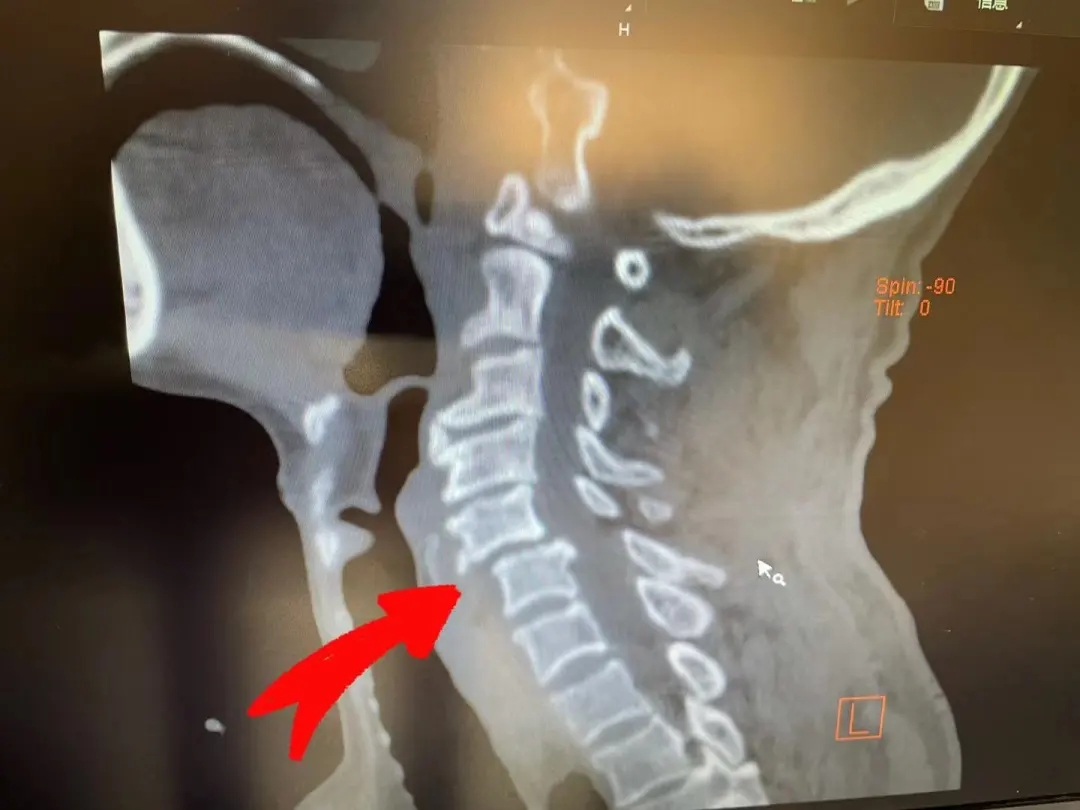

术前影像资料